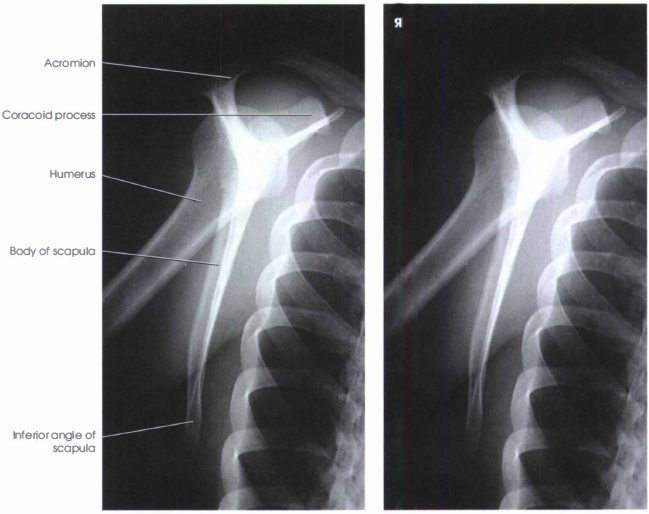

LATERAL PROJECTION RAO OR LAO SCAPULA RadTechOnDuty